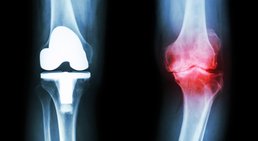

Knieprothese

Als Facharzt für Orthopädie und Traumatologie biete ich meinen Patienten ein breites Spektrum an konservativen Behandlungsmethoden und chirurgischen...

Gerne bespreche ich mit Ihnen die unterschiedlichen Behandlungsmaßnahmen bei Knie- oder Hüftbeschwerden (konservative Möglichkeiten, gelenkerhaltende Operationstechniken); sollte ein künstlicher Gelenkersatz erforderlich sein, biete ich im Bereich der Hüfte die minimal-invasive und im Bereich des Knies die computernavigierte Operationstechnik an. Darüber hinaus bin ich auf Wechseloperationen spezialisiert – Probleme mit bereits bestehenden Kunstgelenken werden von mir umfassend abgeklärt und behandelt, stets mit dem Ziel, dass meine Patienten ihre schmerzfreie Mobilität möglichst rasch wiedererlangen.